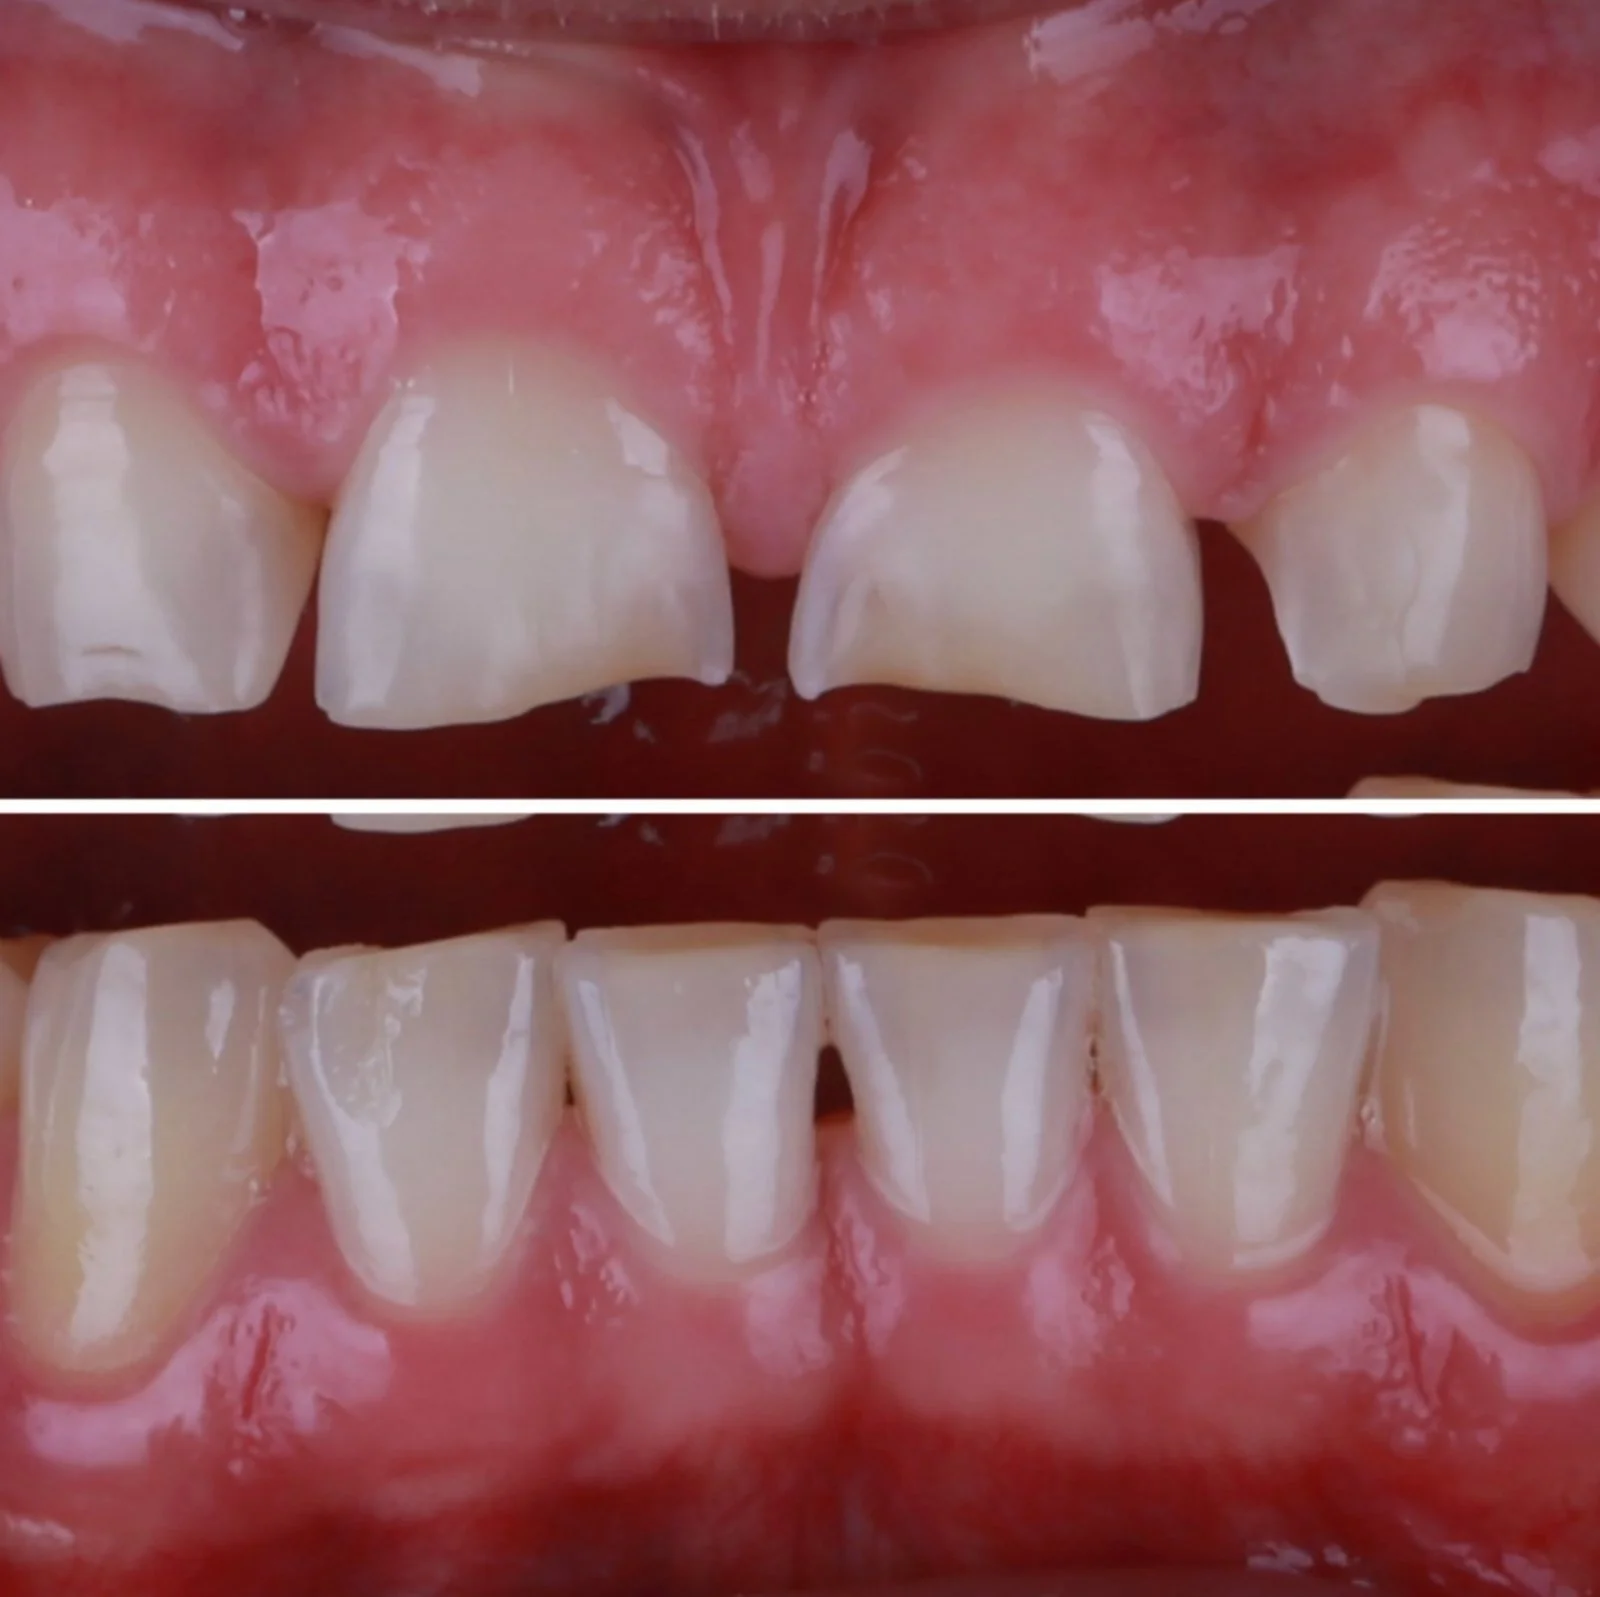

5. Frontal view, upper and lower teeth, bite

• 1:1 magnification.

• The midline of the incisors is the vertical midline of the image.

• The horizontal midline of the image bisects the upper incisors.

• Selected 4-6 teeth are cropped out of the image.

• Show as much of the gingiva as possible.

6. Frontal view of treated teeth, teeth apart (upper or lower: show teeth that have been treated)

• The upper and lower incisors are visible (the ones that have been treated), the gingiva adjacent to the teeth is also visible. The retracted lip and antagonists must not be visible. At this level of magnification, 4-6 upper teeth or 6-8 lower teeth are visible.

• Camera is levelled with the teeth.

• The central incisors are the midline of the image.

Upper front, teeth apart

• No retractors are visible.

• The philtrum and the midline of the incisors are the vertical midline of the image.

• No antagonists are visible.

Lower front, teeth apart